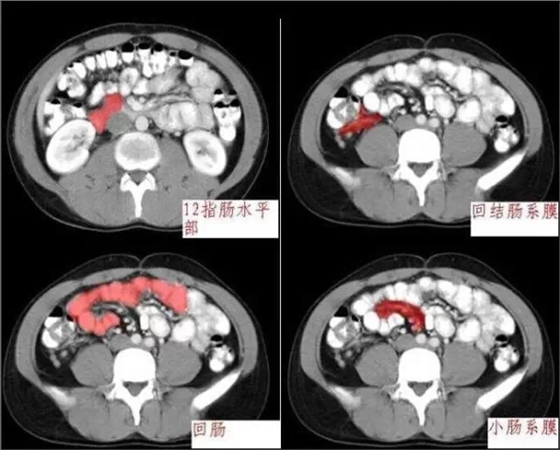

640.webp (1).jpg